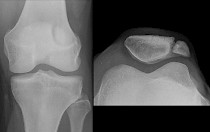

Die Patella partita ist eine Hemmungsfehlbildung der Kniescheibe. Die Kniescheibe bildet sich aus mehreren Knochenkernen, die im Laufe der embryonalen Entwicklung (Ontogenese) verschmelzen. Bleibt diese Verschmelzung aus, entsteht eine im Röntgenbild sichtbare scheinbare Teilung der Kniescheibe.

Das können zwei (Patella bipartita), drei (Patella tripartita) oder mehrere (Patella multipartita) Anteile sein.

Die Veränderung macht in aller Regel keine Beschwerden und wird als Zufallsbefund im Röntgenbild entdeckt. Jungen sind 9 × häufiger betroffen.Typischerweise tritt die Veränderung einseitig und am oberen äußeren Patellaanteil auf. Gelegentlich treten belastungsabhängige Beschwerden auf, ähnlich der Chondropathia patellae.

Die Diagnose wird im Röntgenbild gestellt. Die unverbundenen Anteile finden sich meist im oberen/seitlichen Rand der Kniescheibe.

(Abb. 2).Röntgenbild einer Patella tripartita Die Anteile der Kniescheibe sind im roten Kasten eingefärbt.